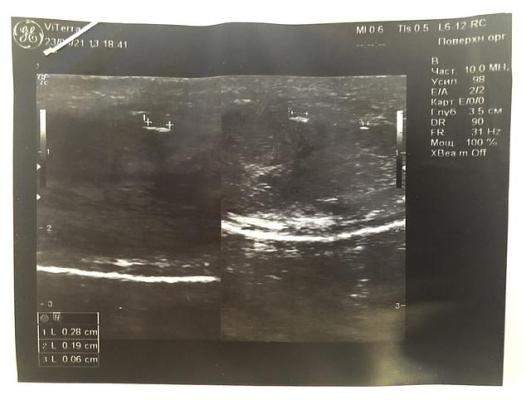

При контрольном УЗИ полового члена (ещё через 3 месяца) фиброзные бляшки не выявлены.